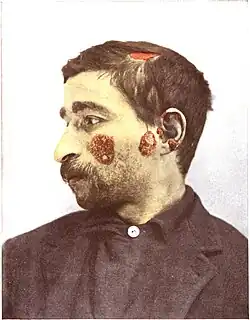

Skin

As many as 70% of people with lupus have some skin symptoms. The three main categories of lesions are chronic cutaneous (discoid) lupus, subacute cutaneous lupus, and acute cutaneous lupus. People with discoid lupus may exhibit thick, red scaly patches on the skin. Similarly, subacute cutaneous lupus manifests as red, scaly patches of skin but with distinct edges. Acute cutaneous lupus manifests as a rash. Some have the classic malar rash (commonly known as the butterfly rash) associated with the disease.[17] This rash occurs in 30–60% of people with SLE.[18]

There are several explanations ventured for the term lupus erythematosus. Lupus is Latin for "wolf",[156][5] and in Medieval Latin was also used to refer to a disease of the skin,[157] and "erythematosus" is derived from ἐρύθημα, Ancient Greek for "redness of the skin". All explanations originate with the reddish, butterfly-shaped malar rash that the disease classically exhibits across the nose and cheeks. The reason the term lupus was used to describe this disease comes from the mid-19th century. Many diseases that caused ulceration or necrosis were given the term "lupus" due to the wound being reminiscent of a wolf's bite. This is similar to the naming of lupus vulgaris or chronic facial tuberculosis, where the lesions are ragged and punched out and are said to resemble the bite of a wolf.[158]

The neoclassical period began in 1851 when the skin disease which is now known as discoid lupus was documented by the French physician, Pierre Cazenave. Cazenave termed the illness lupus and added the word erythematosus to distinguish this disease from other illnesses that affected the skin except they were infectious.[161] Cazenave observed the disease in several people and made very detailed notes to assist others in its diagnosis. He was one of the first to document that lupus affected adults from adolescence into the early thirties and that facial rash is its most distinguishing feature.[162]

Research and documentation of the disease continued in the neoclassical period with the work of Ferdinand von Hebra and his son-in-law, Moritz Kaposi. They documented the physical effects of lupus as well as some insights into the possibility that the disease caused internal trauma. Von Hebra observed that lupus symptoms could last many years and that the disease could go "dormant" after years of aggressive activity and then re-appear with symptoms following the same general pattern. These observations led Hebra to term lupus a chronic disease in 1872.[163]

Kaposi observed that lupus assumed two forms: the skin lesions (now known as discoid lupus) and a more aggravated form that affected not only the skin but also caused fever, arthritis, and other systemic disorders in people.[164] The latter also presented a rash confined to the face, appearing on the cheeks and across the bridge of the nose; he called this the "butterfly rash". Kaposi also observed those patients who developed the butterfly rash were often afflicted with another disease such as tuberculosis, anemia, or chlorisis which often caused death.[162] Kaposi was one of the first people to recognize what is now termed systemic lupus erythematosus in his documentation of the remitting and relapsing nature of the disease and the relationship of skin and systemic manifestations during disease activity.[165]